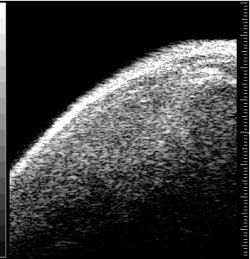

![]() |

Above, ultrasound image of NHL xenograft done on a 20-MHz transducer at five hours after CHOP chemotherapy. The apoptotic areas correspond to the areas of high-intensity backscatter. Below, corresponding histology image with TUNEL stain. The areas that are stained brown correspond to the apoptotic areas. Images courtesy of Dr. Charles Cho.